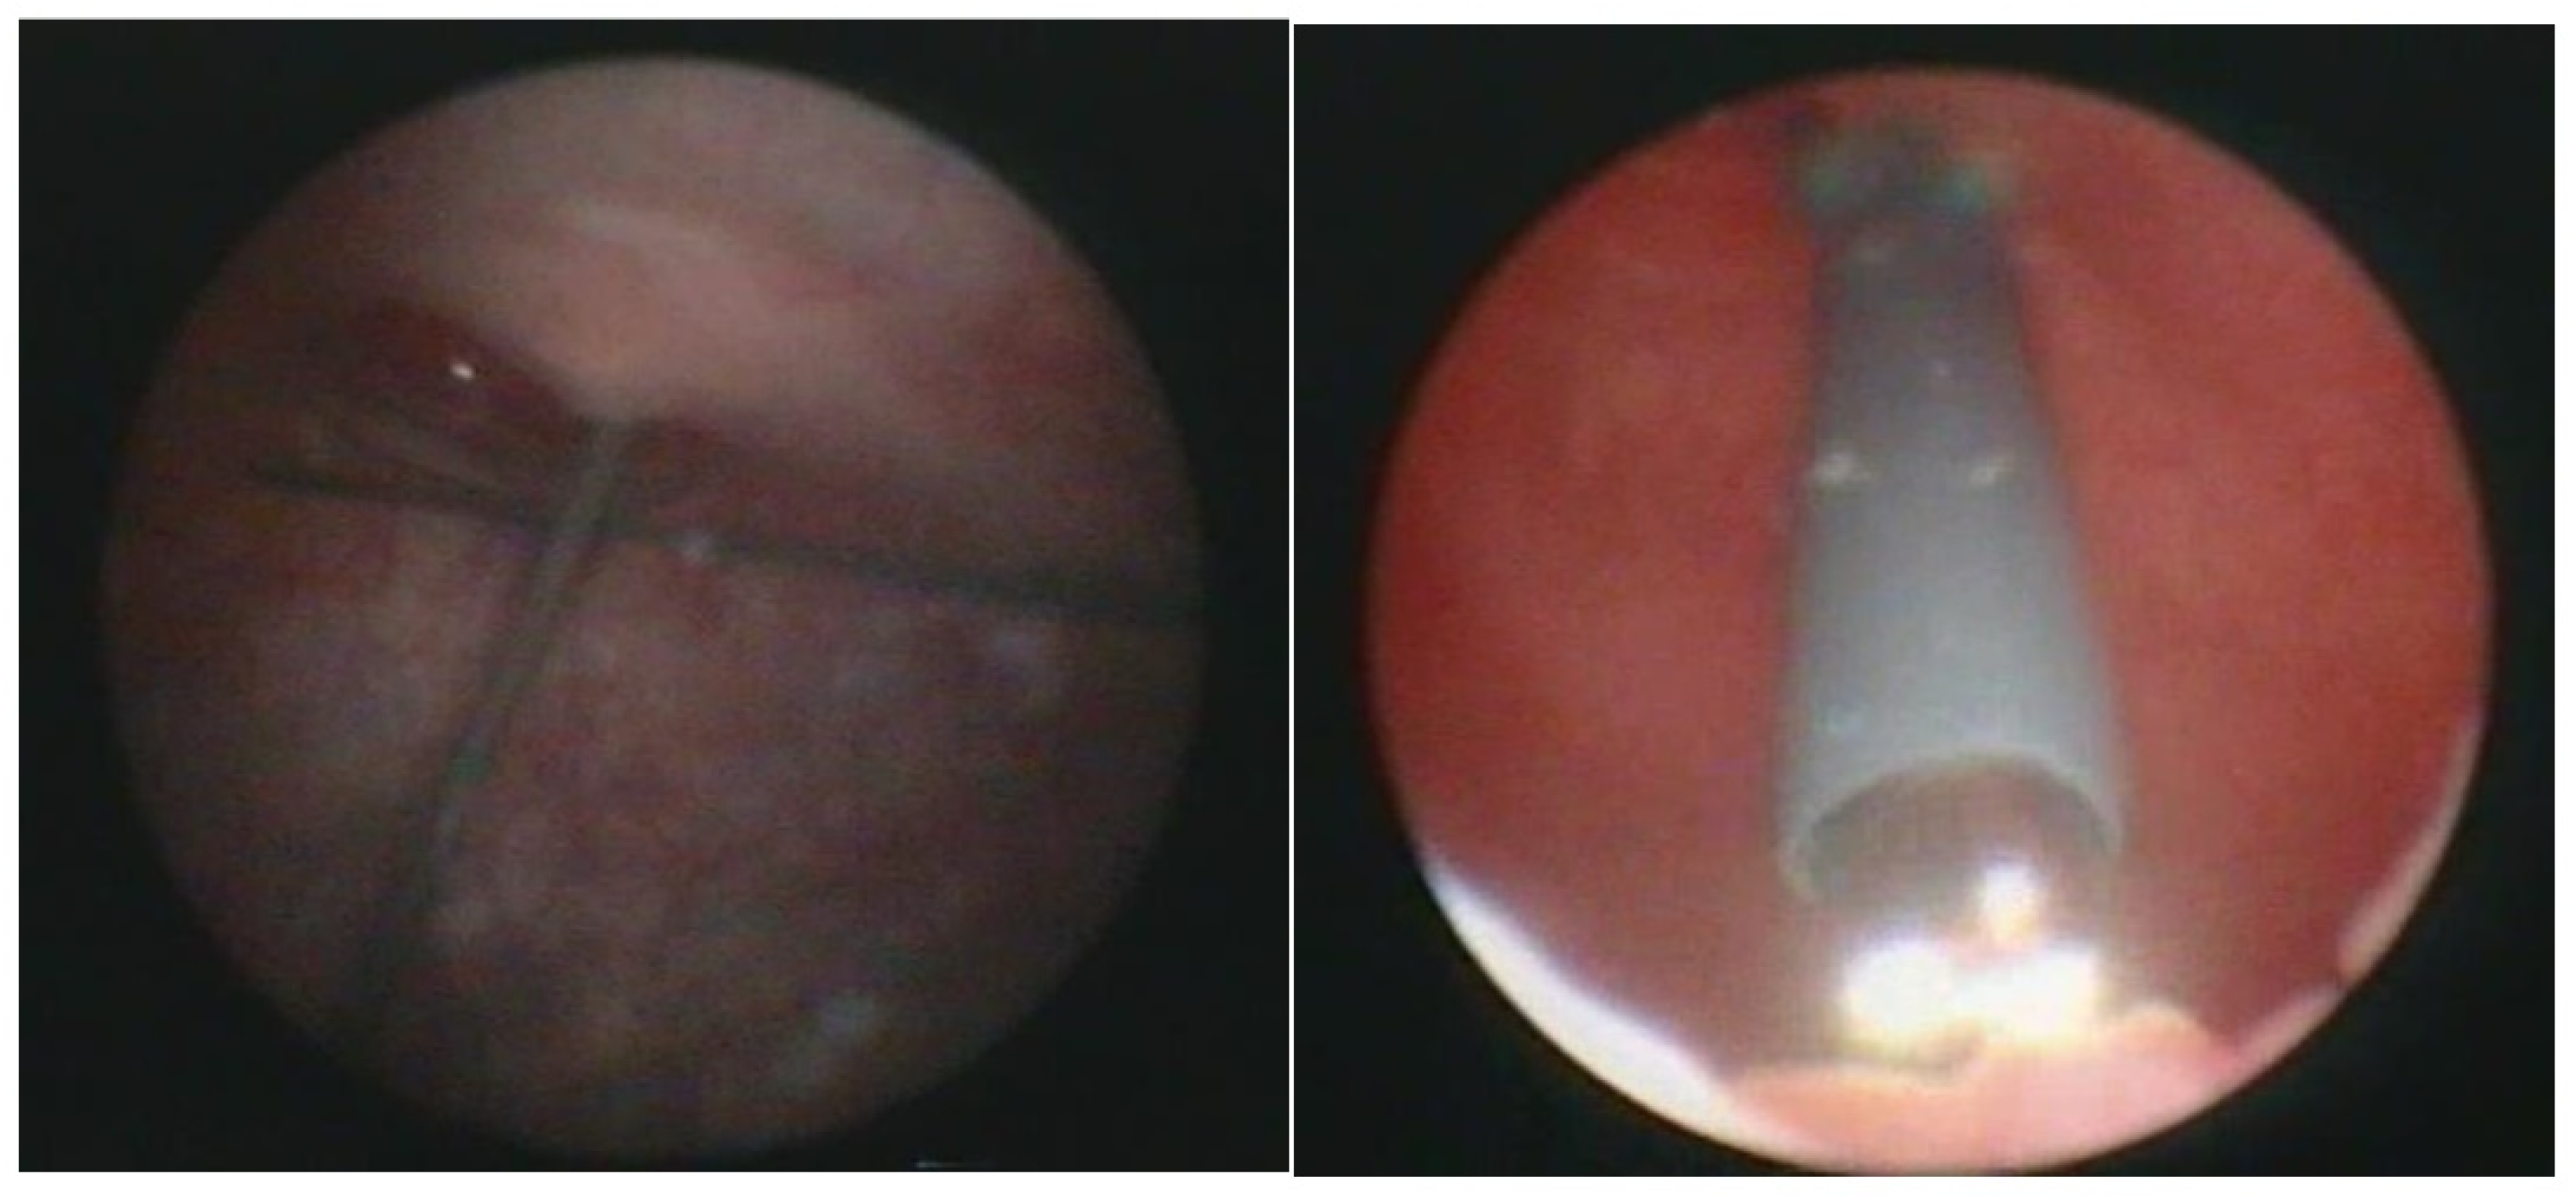

With the patient under general anesthesia in the lithotomy position, antegrade urethrocystoscopy was performed using a 9.5 Fr cystoscope (Figure 1). In parallel, percutaneous suprapubic bladder access introducing a second 9.5 Fr. cystoscope was accomplished. Four quadrant Dx/HA injections were performed, with the two surgeons guiding each other by parallel endoscopy to the optimal localization for injection (Figure 2, Figure 3 and Figure 4). In selected patients, the procedure was completed with transurethral intravesical Botox® injection. At the end of the procedure, a transurethral Foley catheter was placed and left in place for 10 days. Patients were discharged on the first day after surgery and they returned to the outpatient clinic for scheduled removal of the Foley catheter.

Figure 1.

9.5 Fr cystoscope with metal needle (2 sets needed).

Figure 2.

Combined antegrade and retrograde endoscopy.